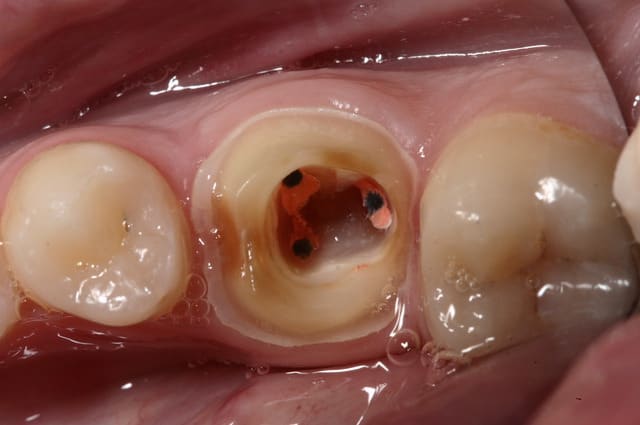

> Je ne vois pas quand un onlay n'est pas indiqué ?

> Même quand il ne reste rien, la preuve ci-dessous.

non mais il n'y a que les fous qui font cela !

jamais ça va tenir, sans IC en plus...

tres joli boulot....